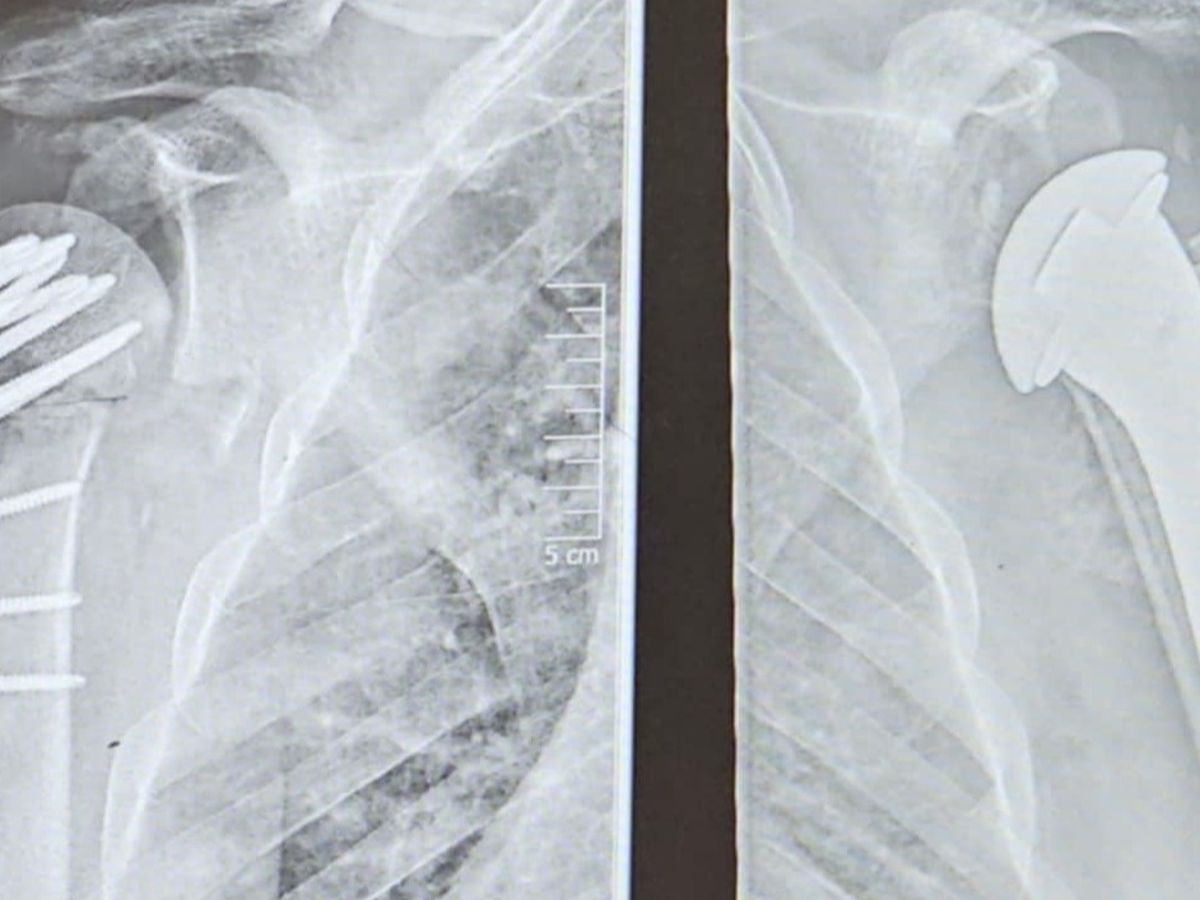

Hi, my name is Pete, and I am reaching out on behalf of my best friend, Michael, who is going through an incredibly tough time. In April, Michael suffered a devastating injury, breaking both of his shoulders. Since then, he has endured four surgeries to repair the damage, but his journey has been far from smooth. The work done on his right shoulder has failed—the bone is no longer viable and is essentially dead. Now, he is facing a complex fifth surgery on December 9 to remove and replace the damaged bone entirely. Michael has been unable to work since his injury, making it difficult for him to support himself. Even the simplest tasks—like sweeping the floor, getting dressed, or carrying a plate—have become impossible. This situation has been emotionally, physically, and financially overwhelming for him. I’m asking for your help to support Michael as he fights to regain his independence and quality of life. Your contributions will go directly toward his medical expenses, daily living costs, and the resources he needs during his long recovery process.